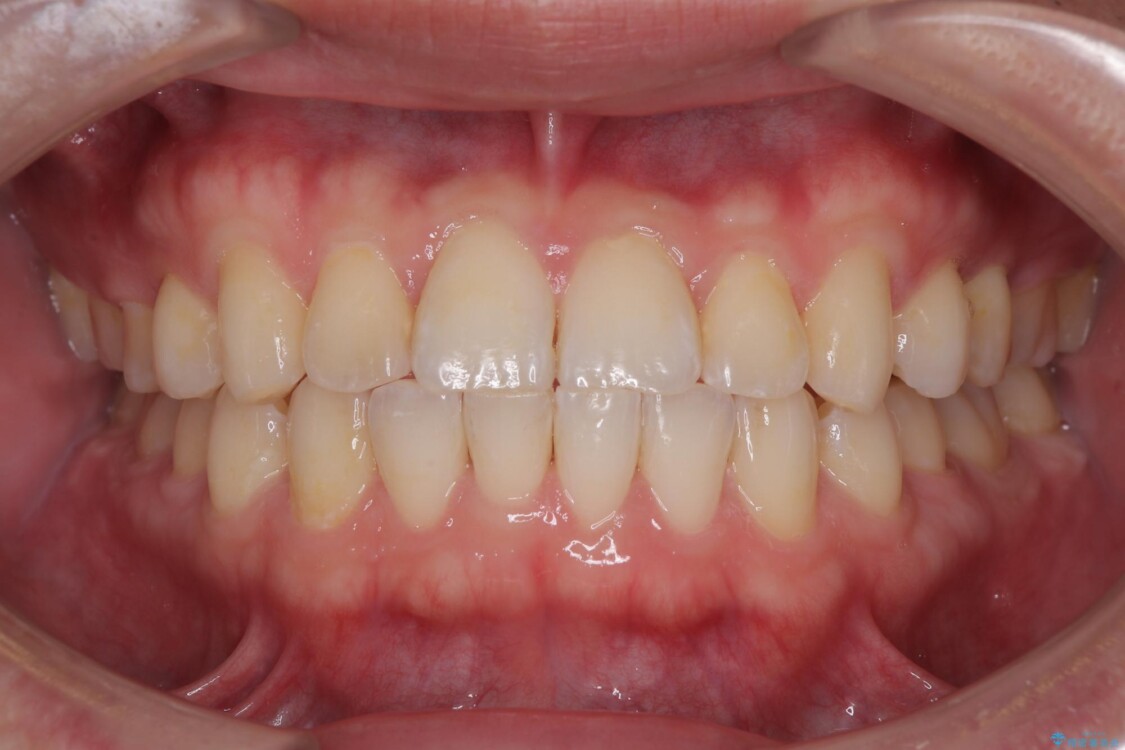

治療後

• 前歯のガタガタ・奥歯のかみ合わせ(シザーズバイト)を改善|1年半で完了したメタルブラケット矯正 治療後画像

**前歯のデコボコ(叢生)**が整い、歯列全体が美しく改善

シザーズバイトの奥歯も正常なかみ合わせに改善

捻転歯も回転が修正され、全体的に清掃性・咀嚼効率が向上

患者様にも「大人になってから矯正を始めることに不安もありましたが、思っていたよりも短期間で治療が終わって本当にうれしいです。前歯のガタガタも気にならなくなり、笑うことに自信が持てるようになりました!」と喜んでいただけました。